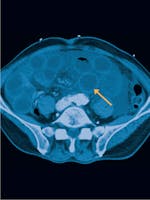

Ischemia mezenterică - Cauze, simptome și tratament

Atunci când fluxul sangvin arterial corespunzător sistemului gastrointestinal este redus, ca urmare a unui blocaj al vaselor de sânge, apare ischemia mezenterică.